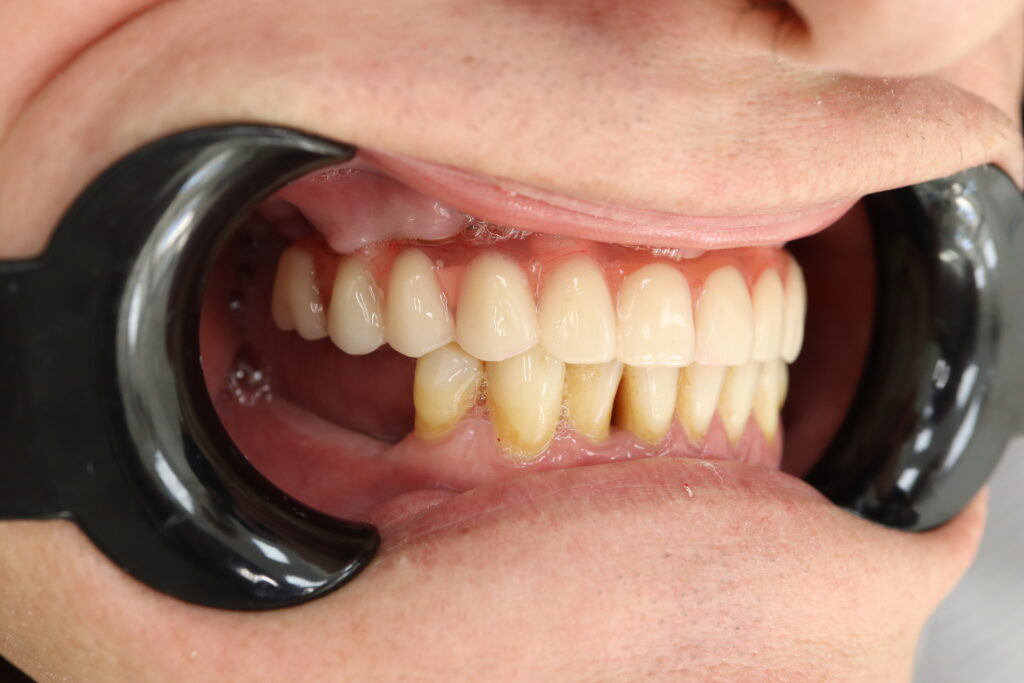

результат протезирования